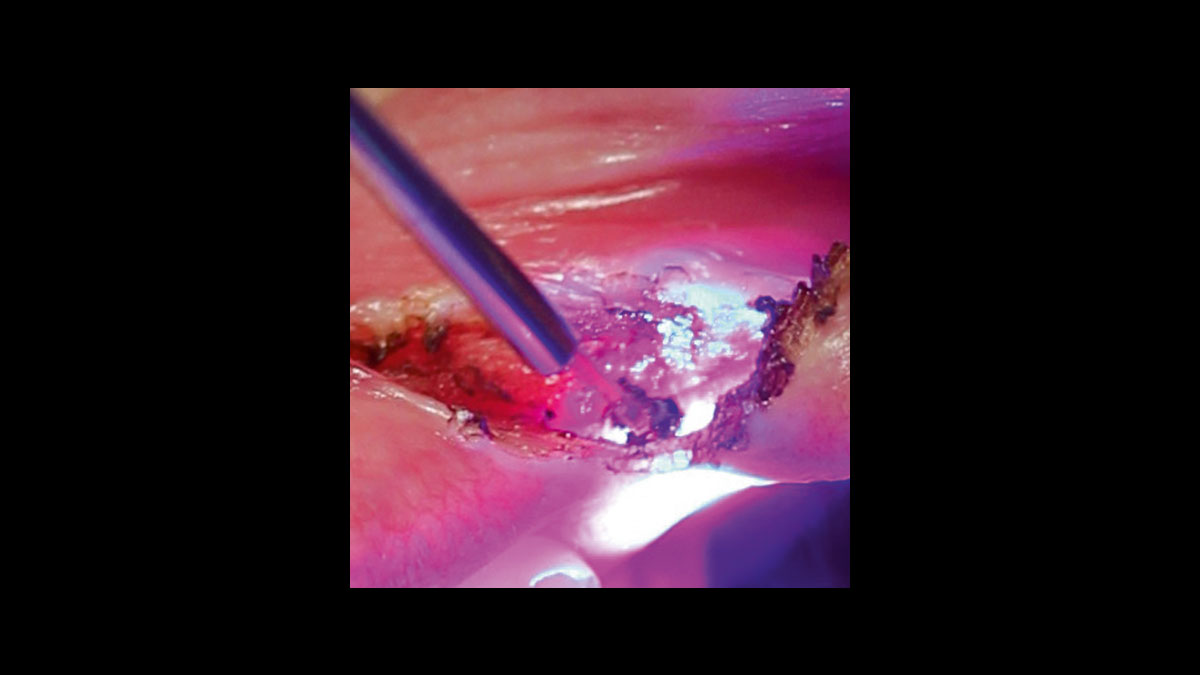

Reducción de gérmenes en periodoncia